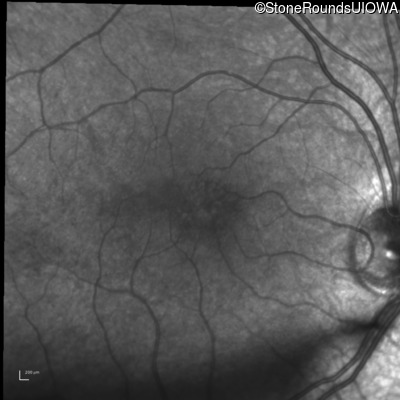

Infrared Fundus Photograph - Right - 20/40 -2

Exemplar